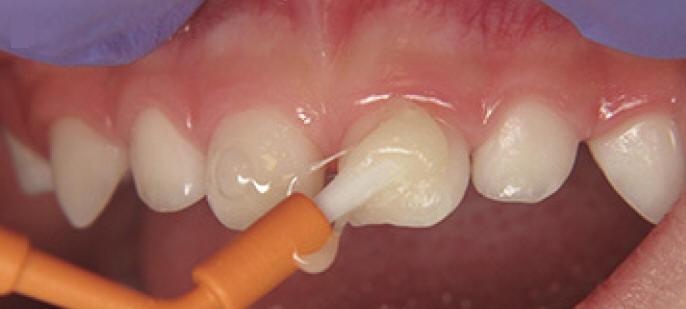

Técnica de aplicación profesional del barniz fluorado (Clinpro White Varnish)

1. Cepillado manual para eliminar placa bacteriana de la superficie dental

2. Ubicar rollos de algodón en el cuadrante que se va a trabajar

3. Secado de los dientes con gasa (figura 1)

4. Aplique una capa delgada de barniz de una sola vez, lo más rápido posible (figura 2) notará que el barniz se vuelve más firme, porque seca muy rápido en ambientes cálidos ó en contacto con los dientes.

5. Secuencia de aplicación:

• Arcada superior desde las molares hasta los incisivos: caras vestibular, proximal, oclusal  y palatino

• Arcada inferior desde las molares hasta los incisivos: caras vestibular, proximal, oclusal  y palatino (figura 3)

6. Luego de la aplicación del barniz el paciente no debe comer nada por las siguientes dos horas, solo puede beber agua.

7. No se debe cepillar los dientes el día de la aplicación.